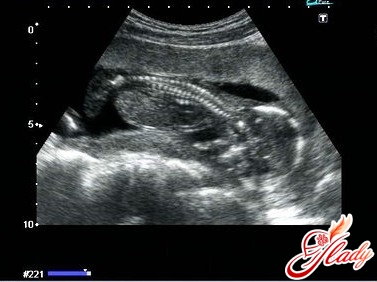

Беременность 15 неделя симптомы. К этому сроку и будущие родители, и родственники успевают осознать скорое прибавление в семье, поэтому стремятся помочь и поддержать будущих родителей. Внимание и поддержка сейчас особенно важны как для мамы, так и для ребенка, беременность 15 неделя УЗИ уже покажет вашего ребенка во всей красе, поэтому начиная с этого срока на УЗИ можно и нужно приезжать вдвоем.